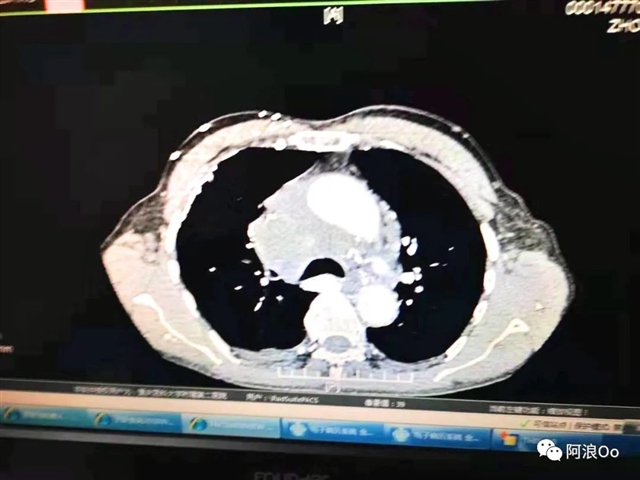

电刀辅助下经气管纵隔活检钳取活检技术(Cautery Assist Transbronchial For cep Biopsy,Ca-TBFB):超声支气管镜引导,经过气管软骨环用针形电刀切开气管粘膜进入纵隔,以活检钳进行纵隔钳取活检。相对于传统TBNA和eBUS-TBNA,能够取得大块组织标本,对于纵隔良性疾病、淋巴瘤具有明显优势。淋巴结坏死明显,多次eBUS-TBNA拿不到病理依据,可以作为备选技术。

擅长于呼吸内科疑难危重病人的诊治,尤其在晚期肺癌的微创介入治疗及肺部微小结节的诊治方面有较为深入的研究。拓展eBUS(超声支气管镜)的深入应用,首先在国内开展电刀辅助下纵膈活检钳取活检(Ca-TBFB)技术, 在国内较早开展超声支气管镜引导下纵膈粒子植入消融技术,解决了众多纵膈疑难疾病的诊治问题。先后发表SCI及CSCD论文10余篇,以编委身份参与人民卫生出版社《内科学》教材一部